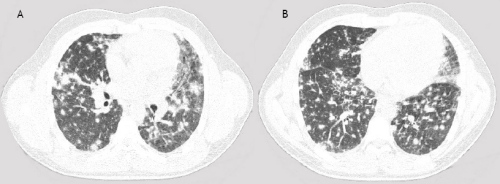

A 22-years old male presented with dyspnea, non-productive cough, myalgia and fever. These symptoms started 4 days prior to admission. His medical history was unremarkable. He smoked tobacco for a few years. Finally, he admitted alcohol abuse, heavy marijuana and cocaine smoking in the last months. Physical examination revealed some crackles at auscultation, he was a little tachypnoeic (20 breaths•min–1) and his body temperature was 36.8°C. He had a moderate hypoxemia (pO2 8.7kPa, breathing room air), high serum C-reactive protein (254 mg/l), a white blood cell count of 16.3 109•L–1 and a normal number of eosinophils. Figure 1 shows his chest roentgenogram demonstrating diffuse infiltrates at presentation. Figure 2 shows his high resolution CT (HRCT) scan with a diffuse reticulonodular pattern ad admission. Spirometry two days after admission showed normal dynamic lung volumes with slightly decreased diffusing capacity (81% of predicted).

Figure 2 The HRCT shows irregular nodular abnormalities, no signs of pleural effusion or hilar node enlargement.